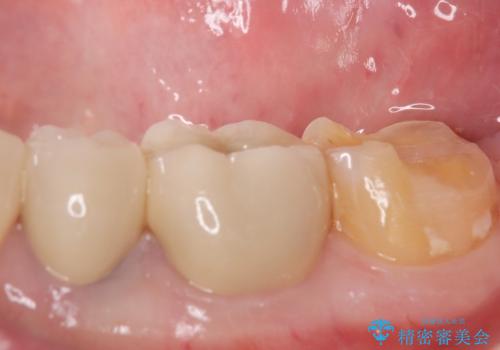

- 過去に治療したゴールドの詰め物が取れて来院。取れたのは2回目だそうです。レントゲンでは適合が良いので再装着可能だったが、

もう取れたくないとの事だったので被せ物のご案内をしました。ゴールドの被せ物の希望だったのでゴールドクラウンでの治療になりました。

適合の良いゴールドクラウンが入りました。

ゴールドは適合が良く、割れる心配もありません。

また、虫歯になるリスクも銀歯と比べて低くなります。